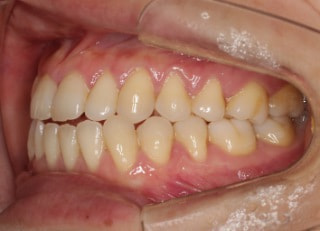

治療後(2年4ヶ月後)